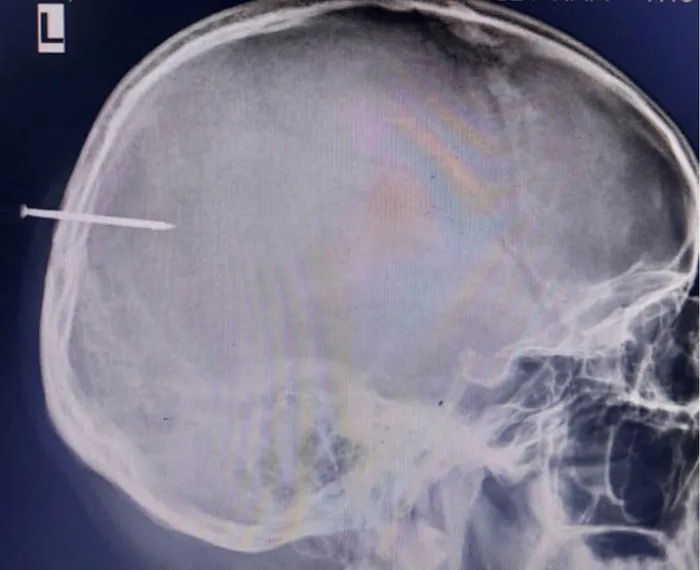

Bị đinh sắt ghim vào trúng đầu, một thanh niên ở thị xã Quảng Yên, Quảng Ninh được Bệnh viện Việt Nam – Thụy Điển Uông Bí phẫu thuật loại bỏ dị vật thành công.

Thông tin từ Bệnh viện Việt Nam – Thụy Điển Uông Bí cho biết, Bệnh viện vừa tiếp nhận và phẫu thuật lấy bỏ dị vật cho một bệnh nhân nam 21 tuổi ở thị xã Quảng Yên, Quảng Ninh bị một chiếc đinh sắt ghim vào đầu.

Ngay lập tức các bác sĩ đã tiến hành chụp X-Quang và CT.Scanner sọ não.

Từ kết quả cho thấy có hình ảnh kim loại vùng chẩm trái đâm xuyên qua xương sọ vào nhu mô não khoảng 16mm.

Sau khi hội chẩn, các bác sĩ chỉ định phẫu thuật lấy bỏ dị vật cho người bệnh.

Nam thanh bị đinh sắt dài 5cm đâm vào đầu được bác sĩ BV Việt Nam -Thụy Điển Uông Bí phẫu thuật thành công

Theo các bác sĩ, trước khi tiến hành phẫu thuật cho người bệnh, bác sĩ đã phải tiên lượng nhiều phương án để kịp thời ứng phó. Trong quá trình phẫu thuật, kip mổ nhận thấy, cây đinh sắt dài gần 5 cm xuyên qua xương sọ và đâm thủng màng cứng vào nhu mô não làm chảy máu màng não và chảy máu nhu mô não.

Các bác sĩ đã tiến hành cầm máu, xử trí tổn thương và lấy cây đinh ra ngoài.

Sau phẫu thuật hiện sức khỏe người bệnh ổn định, tỉnh táo, ăn uống tốt.

Cũng theo bác sĩ, các vết thương sọ não do dị vật thường là vết thương bẩn, việc xử trí nhanh chóng tổn thương và lấy dị vật ra ngoài sớm rất quan trọng sẽ giúp người bệnh tránh được nhiều biến chứng như nhiễm trùng, viêm màng não, áp xe não… nặng có thể liệt toàn thân.